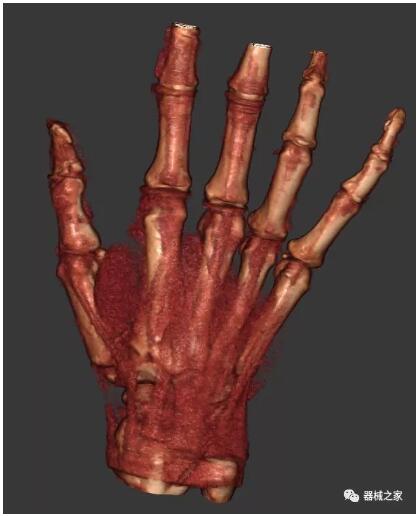

以下是這些“特立獨(dú)行”的CT所拍出來的圖像: